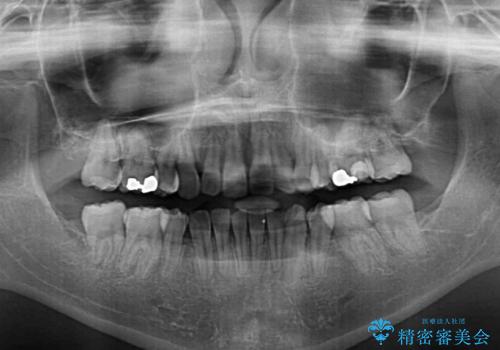

下顎小臼歯の欠損により過蓋咬合となっていたため、下顎は臼歯を起こすことで咬み合わせを改善し、八重歯は第一小臼歯2本を抜歯し、補助装置を使用して速やかに改善することとしました。

著しい過蓋咬合の改善が必要であった割には、治療期間は2年強と標準的でした。